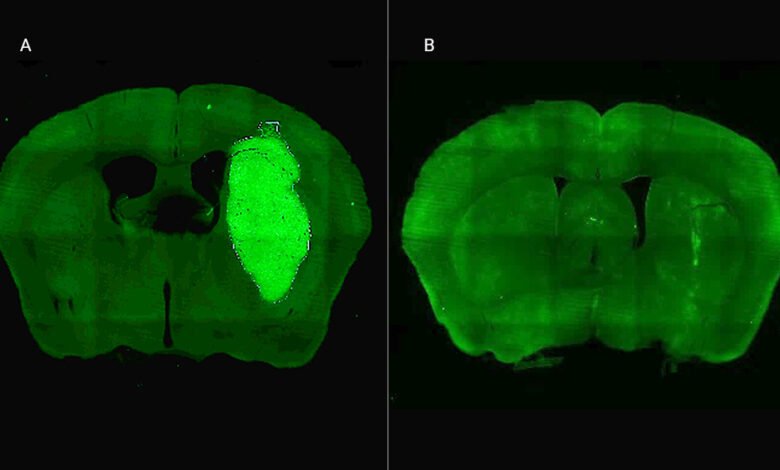

En los estudios in vivo, el equipo trabajó con ratones a los que se les indujeron tumores cerebrales con características similares a las humanas. Para administrar el tratamiento, los investigadores desarrollaron un vector adenoviral capaz de expresar el péptido P60 directamente dentro de las células tumorales. Esta estrategia permitió una acción localizada y sostenida en el tumor, reduciendo el riesgo de efectos adversos en otras partes del organismo.

“Una sola inyección intratumoral inhibió el crecimiento del tumor y mejoró notablemente la respuesta a la quimioterapia, logrando la erradicación del tumor y una sobrevida prolongada en un tercio de los ratones tratados con la terapia combinada”, detalló Candolfi. Los investigadores no observaron efectos neurotóxicos, lo que sugiere un perfil de seguridad favorable en esta etapa experimental.